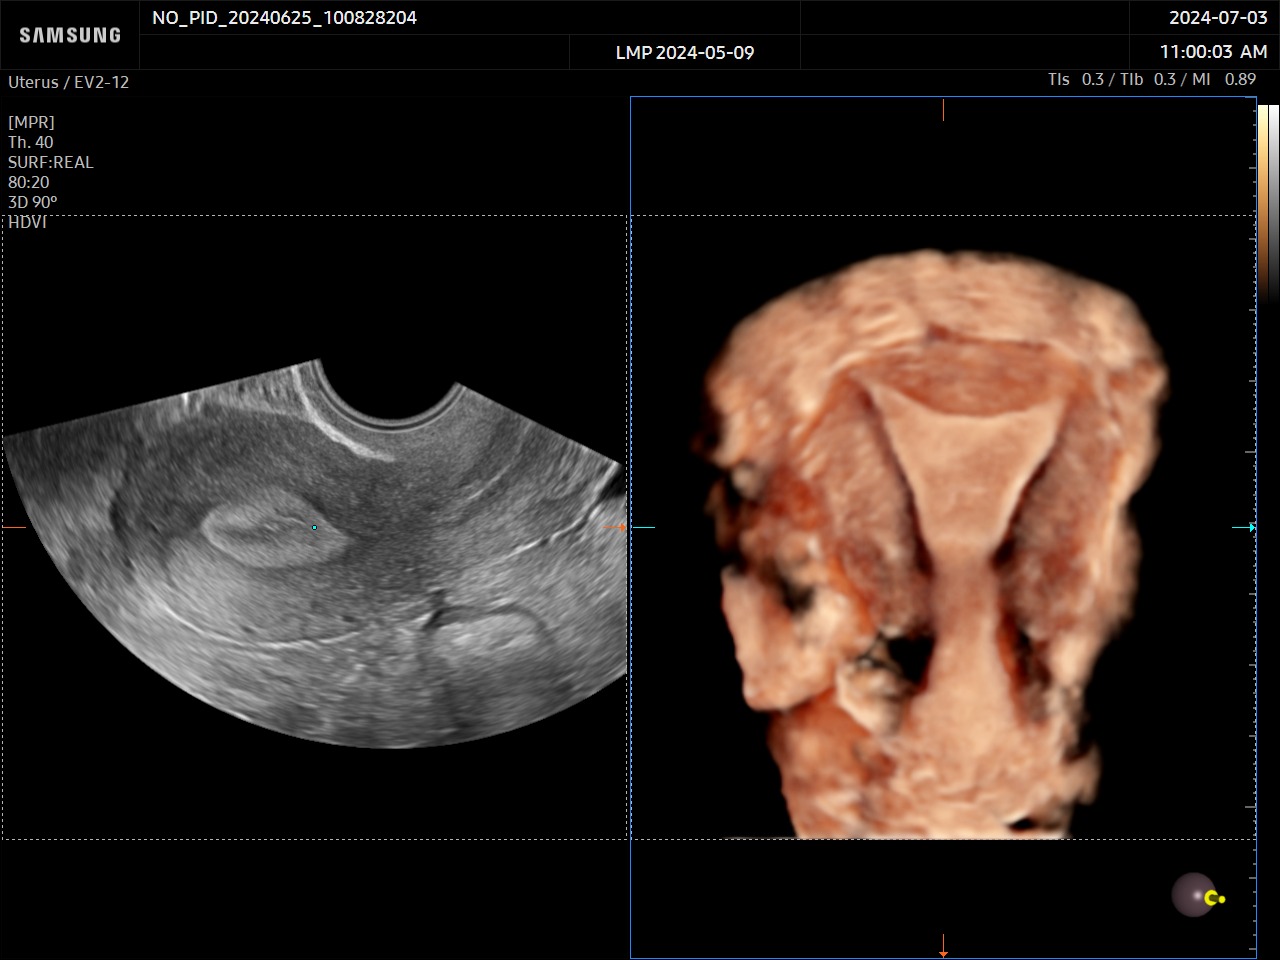

L’outil UterineContour™ permet une reconstruction automatique de la coupe frontale de l’utérus à partir d’une coupe sagittale. Le tracé de la ligne de reconstruction se fait donc automatiquement et l’épaisseur de coupe est ajustée en fonction de l’épaisseur endométriale. De plus, ce mode offre la possibilité d’utiliser la classification des malformations utérines de l’ESHRE / ESGE et de l’ASRM*.

*ESHRE/ESGE : Société européenne de reproduction humaine et d’embryologie/ Société européenne de l’endoscopie gynécologiqueASRM : Société américaine de la médecine reproductive